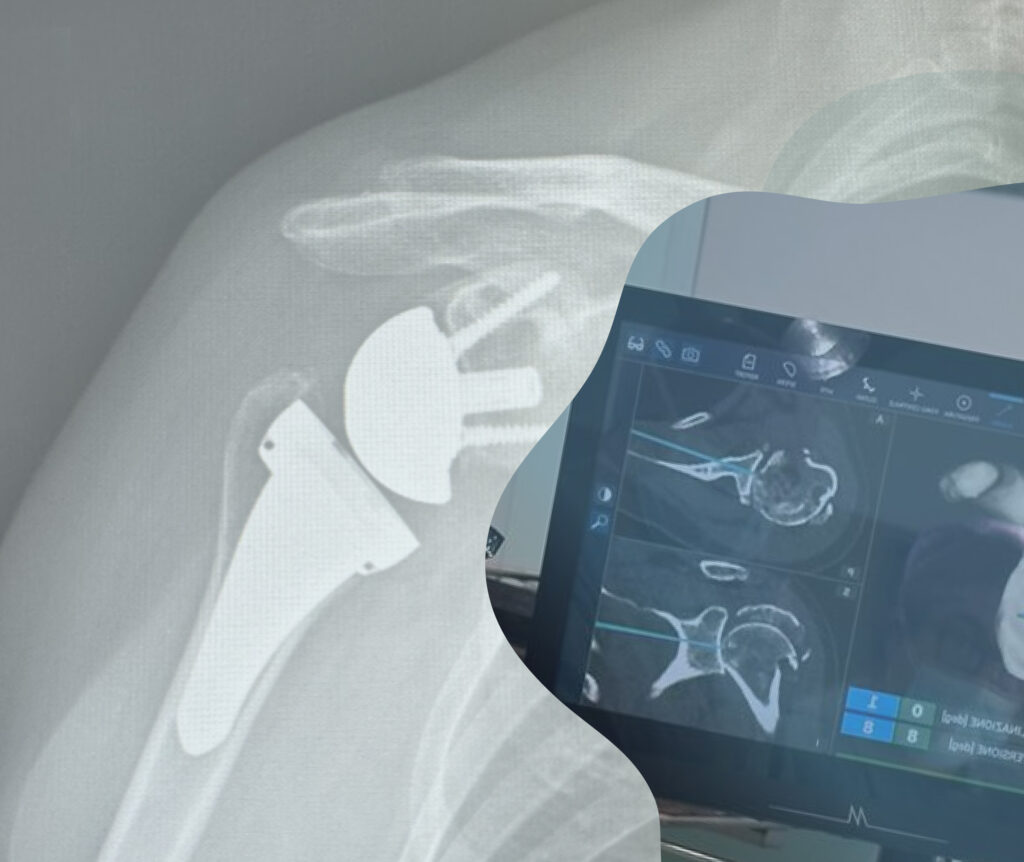

Spalla

La spalla è un complesso di articolazioni che unisce l’arto superiore al tronco e alla testa ed è caratterizzata da 5 articolazioni: 3 articolazioni vere (gleno-omerale, acromio-clavicolare e esterno-clavicolare) e 2 articolazioni funzionali (scapolo-toracica e sotto-acromiale).